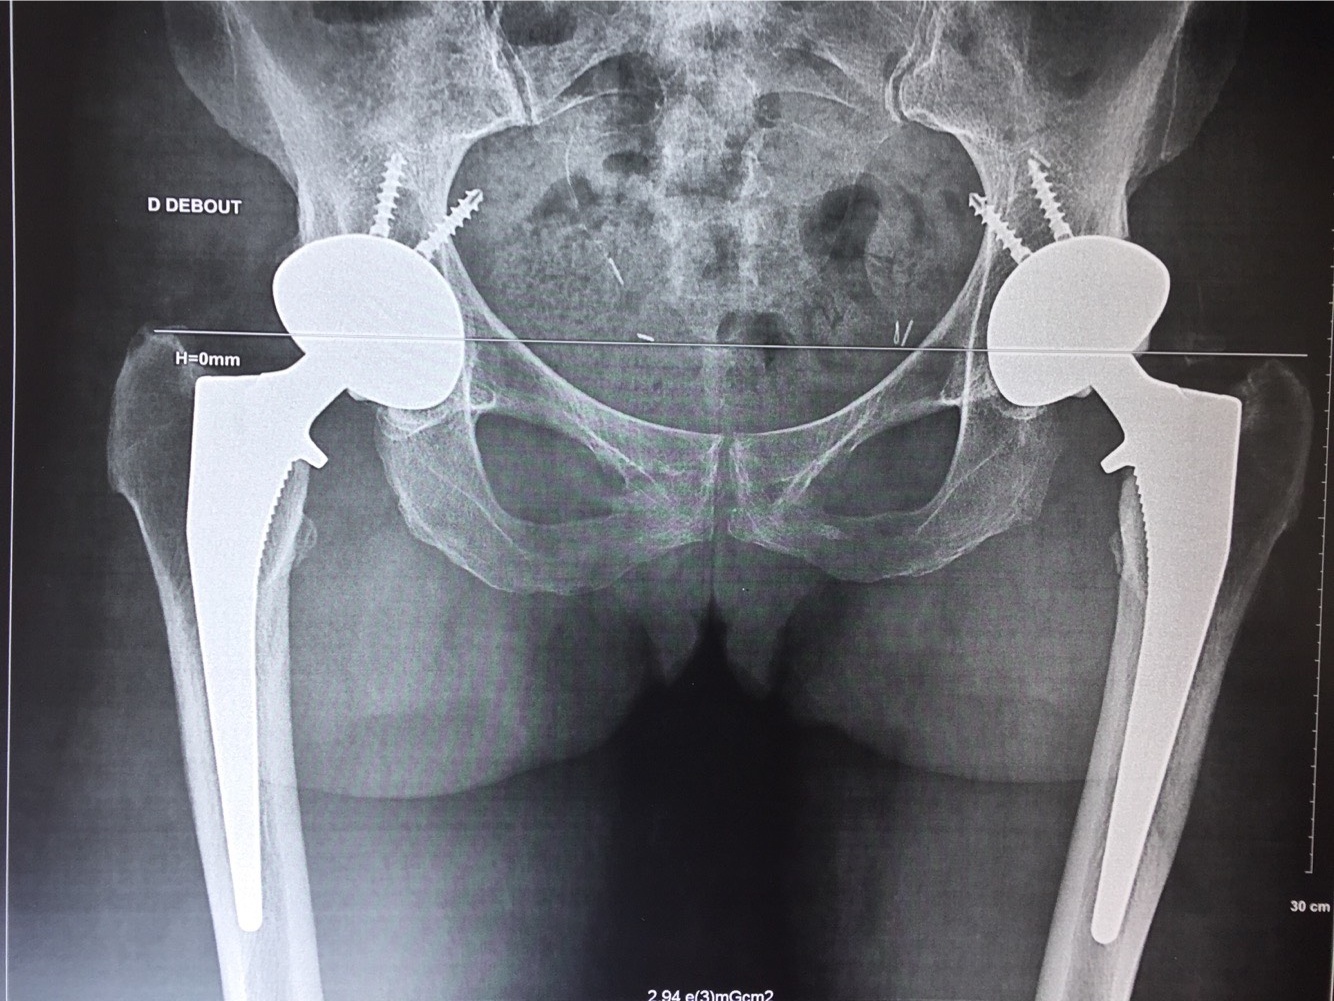

Le traitement sera initialement médical et conservateur : antalgiques, anti inflammatoires, rééducation. Des infiltrations sont possibles mais sont moins efficaces que dans le genou compte tenu que la hanche est une articulation profonde. En cas d'échec ou d'impossibilité de traitement médical, il sera chirurgical avec mise en place d'une prothèse totale de hanche (PTH). La reprise et la pratique du sport avec une PTH est possible selon le type de prothèse mise en place et le niveau d'impact du sport. Elle sera toujours progressive.